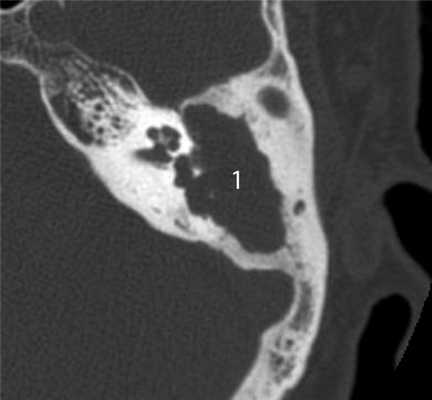

КТ-признаки злокачественной опухоли височной кости предопределяются происходящими в ней патоморфологическими изменениями. Так, наличие опухолевых масс в среднем ухе на КТ проявляется нарушением пневматизации полостей среднего уха (рис. 1). Рисунок 1. Лангергансоклеточный гистиоцитоз. Аксиальная проекция правой височной кости. Отсутствует пневматизация полостей среднего уха за счет наличия опухоли (1), вызывающей обширные деструктивные изменения в пирамиде. Цепь слуховых косточек сохранена (2). Степень выраженности данного КТ-симптома обусловлена размерами самой опухоли и ее точной локализацией в височной кости. Нарушение пневматизации полостей среднего уха не является специфичным для новообразований и постоянно встречается при других заболеваниях среднего уха, в первую очередь при остром и хроническом средних отитах.

Частым проявлением опухоли височной кости, как было сказано выше, является ее распространение в наружный слуховой проход, что находит свое отражение и на КТ. При небольших размерах полипозного новообразования на КТ в просвете наружного слухового прохода визуализируется образование, исходящее из барабанной полости или проникающее в слуховой проход через его разрушенную стенку (рис. 2). Рисунок 2. Лангергансоклеточный гистиоцитоз. Коронарная проекция правой височной кости. В наружном слуховом проходе определяется полипозное образование (1), на уровне которого верхняя стенка НСП деструктивно изменена. Нарушена пневматизация среднего уха (2). Большой «полип» проявляется на КТ полной обтурацией воздушного просвета слухового прохода мягкотканным образованием (рис. 3). Рисунок 3. Рабдомиосаркома. Аксиальная проекция левой височной кости. Отсутствует пневматизация костного устья слуховой трубы и барабанной полости (1). Просвет наружного слухового прохода обтурирован мягкотканным полипозным образованием (2). Деструкция задней стенки барабанной полости и наружного слухового прохода (3). При анализе данного КТ-признака следует учитывать, что истинные полипы, встречающиеся при хроническом гнойном среднем отите, в отличие от опухолей имеют излюбленную локализацию и чаще всего исходят из верхних отделов барабанной полости.